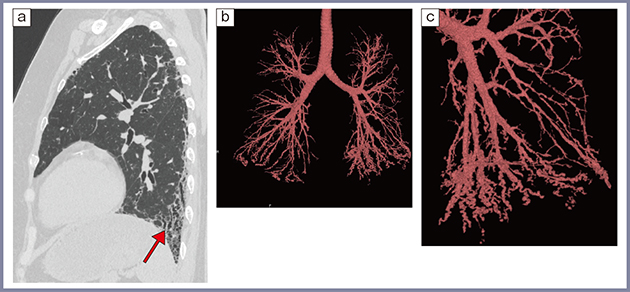

これまで述べたように,Aquilion Precisionでは,末梢の気管支の描出能が向上し,1024×1024マトリックス,0.25mm厚の高精細画像を基に,3Dワークステーション(WS)を用いて末梢の気管支を抽出し,3D画像で観察することが可能になった(図6)。われわれは,これを用いて間質性肺炎における気道病変の定量化に取り組んでいる。

リウマチ肺では,気管支壁への炎症細胞浸潤や気管支壁の肥厚,壁の破壊が起こり,閉塞性細気管支炎や破壊性細気管支炎を来す。リウマチ肺では比較的軽症の場合や間質性肺炎が認められない症例でも気道病変が見られることがしばしばあり,病態の把握のためには気道病変の定量化が重要となる。

ところで,慢性閉塞性肺疾患(COPD)の領域では気管支全体の内腔体積を算出し肺全体の体積に対する割合を求める手法(AWV%)が提案され,COPDの臨床症状や各種指標と相関することが報告されている7)。また,田辺らは,高精細CTではより細い気管支の描出能が向上し正確に測定できる可能性があることを報告している8)。

われわれはこれをリウマチ肺に応用し,Aquilion Precisionで撮影した1024×1024マトリックスの画像をWSで解析し,右肺下葉の体積に対する右肺下葉気管支の体積の割合(AWV%rl)を測定した。当施設の小口らの検討では,DLcoなどの呼吸機能検査との相関が見られ,リウマチ肺の評価に有用と考えられた9)。

図6 50歳代,女性,関節リウマチに伴う間質性肺炎

a:高精細CT矢状断像 b:気管支3D画像 c:気管支3D画像の左肺の拡大像